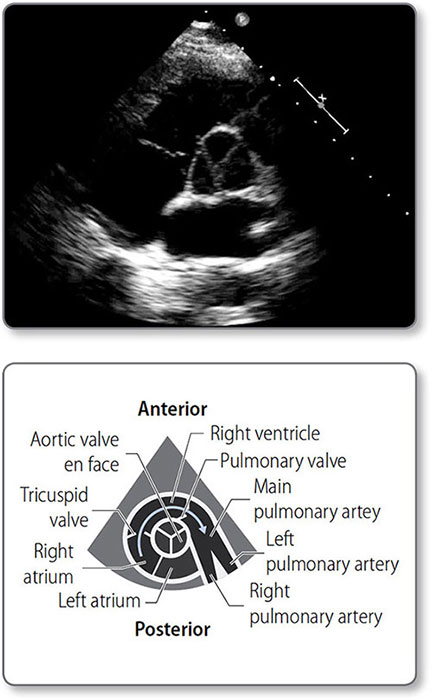

Figure 1.5: Anatomy of the heart valves. ① Aortic valve. ② Pulmonary valve. ③ Mitral valve. ④ Tricuspid valve.

Figure 1.6: Transthoracic echocardiogram showing the circular left ventricle (LV). The lower pressure right ventricle (RV) accommodates the higher pressure left ventricle.